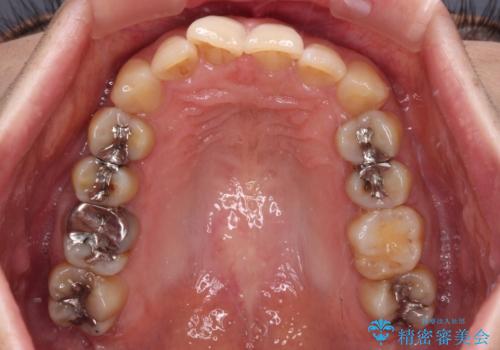

ディープバイトと前歯のデコボコ インビザラインによる矯正治療

- 前歯のディープバイトと叢生を気にして来院された患者様です。

目立ちにくい装置を希望されていたため、ワイヤー装置とインビザラインを提案したところ、インビザラインを希望されました。

下顎大臼歯が手前に倒れていたため、起き上がらせることで咬み合わせ高さを挙上し、ディープバイトと叢生を改善することとしました。

インビザライン特有の奥歯の噛みにくさが治療後半に発言しましたが、無事に終了させることができました。